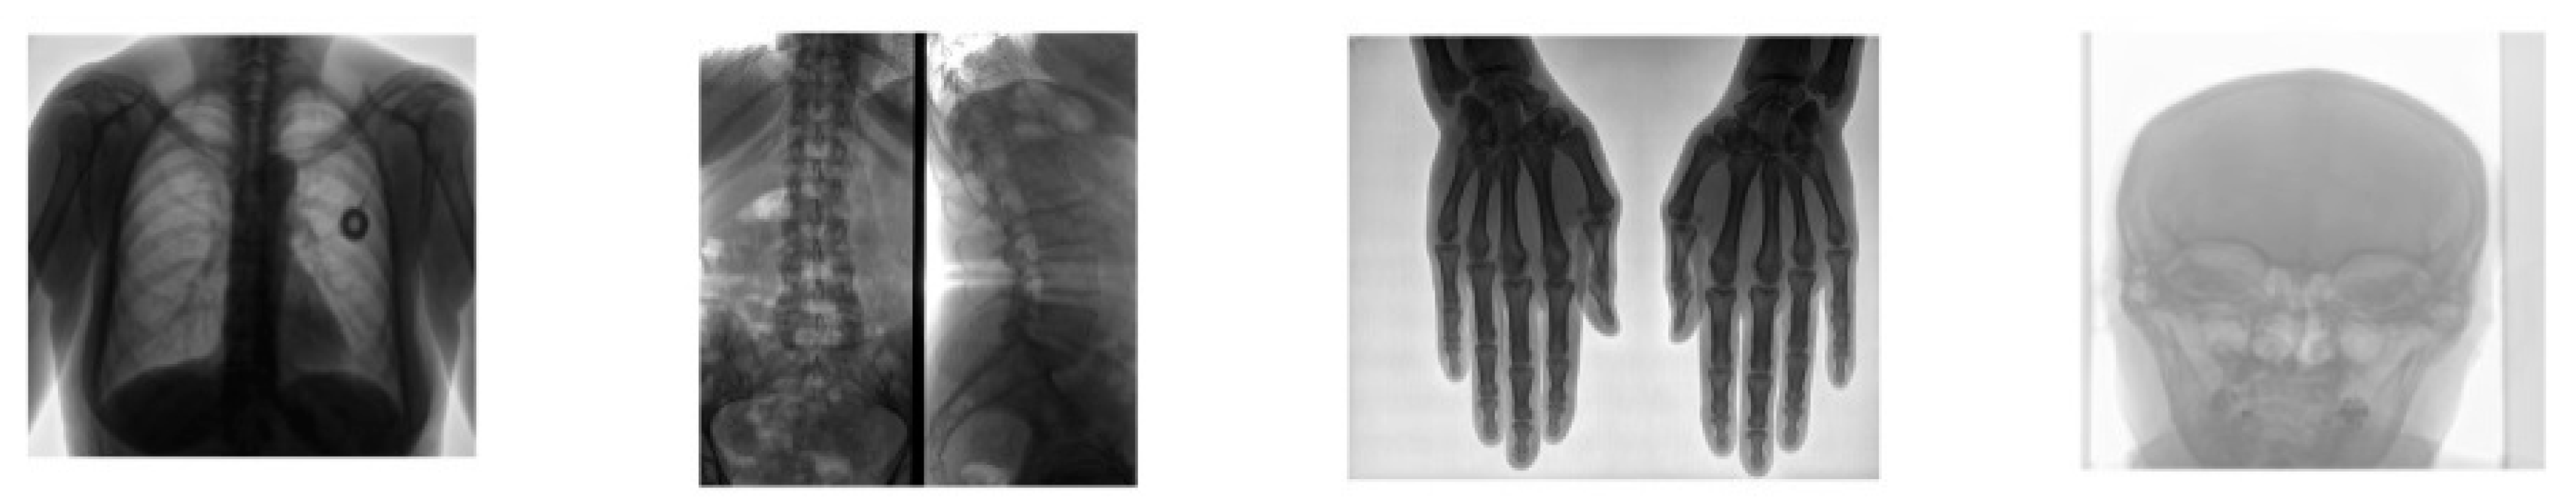

| Image | SSIM | PSNR |

|---|---|---|

| Chest | 0.9861 | 38.15 |

| Tspine | 0.9895 | 37.77 |

| Hands | 0.9997 | 49.52 |

| Skull | 0.9995 | 52.89 |